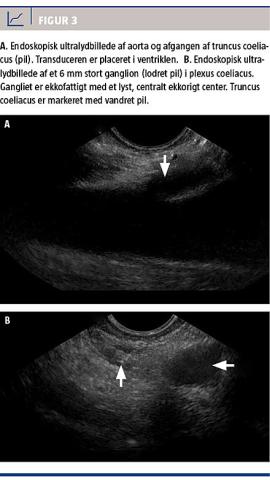

Proceduren foretages med patienten i enten dyb sedation eller generel anæstesi. Endoskopet med den lineært skannende transducer (Figur 2) føres ned i ventriklen, hvor aorta med afgangen af truncus coeliacus og arteria mesenterica superior tydeligt kan ses (Figur 3A). Hos en stor andel af patienterne kan man vha. EUS påvise selve ganglierne i plexus coeliacus som små ekkofattige strukturer med et ekkorigt center (Figur 3B).